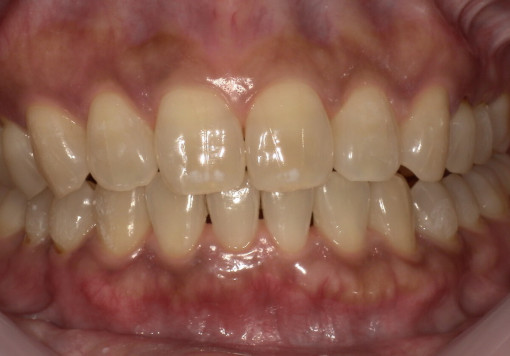

Case 02

before

after

- 主訴:悪いところは治したい

- 治療内容:インプラント、審美補綴、

マウスピース矯正 - 治療期間:40万円

- 診断結果:歯の欠損、歯列不正

- 治療後経過:経過良好

- 治療費用:160万円

リスク・副作用:治療期間が長い、外科的侵襲がある